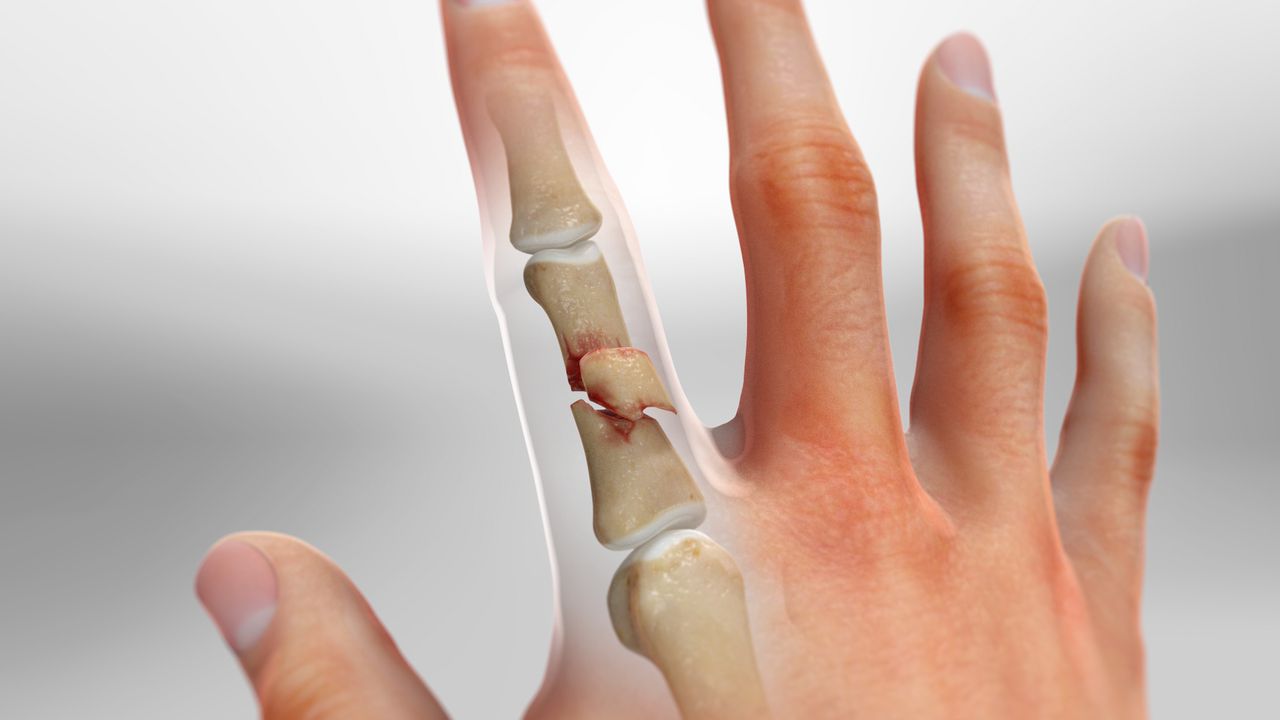

골절의 주요 분류

- 횡골절(Transverse fracture): 뼈가 수평 방향으로 부러져 평면이 단순한 형태.

- 사선·나선 골절(Oblique/Spiral fracture): 힘이 비스듬히 작용해 길게 갈라지는 형태.

- 분쇄 골절(Comminuted fracture): 강한 충격으로 두 조각 이상 파편화.

- 관절내 골절(Intra-articular fracture): 관절면까지 골절선이 침범해 향후 관절염 위험 ↑.

- 탈구 동반 골절(Fracture-dislocation): 골절과 함께 관절 위치가 어긋난 상태.